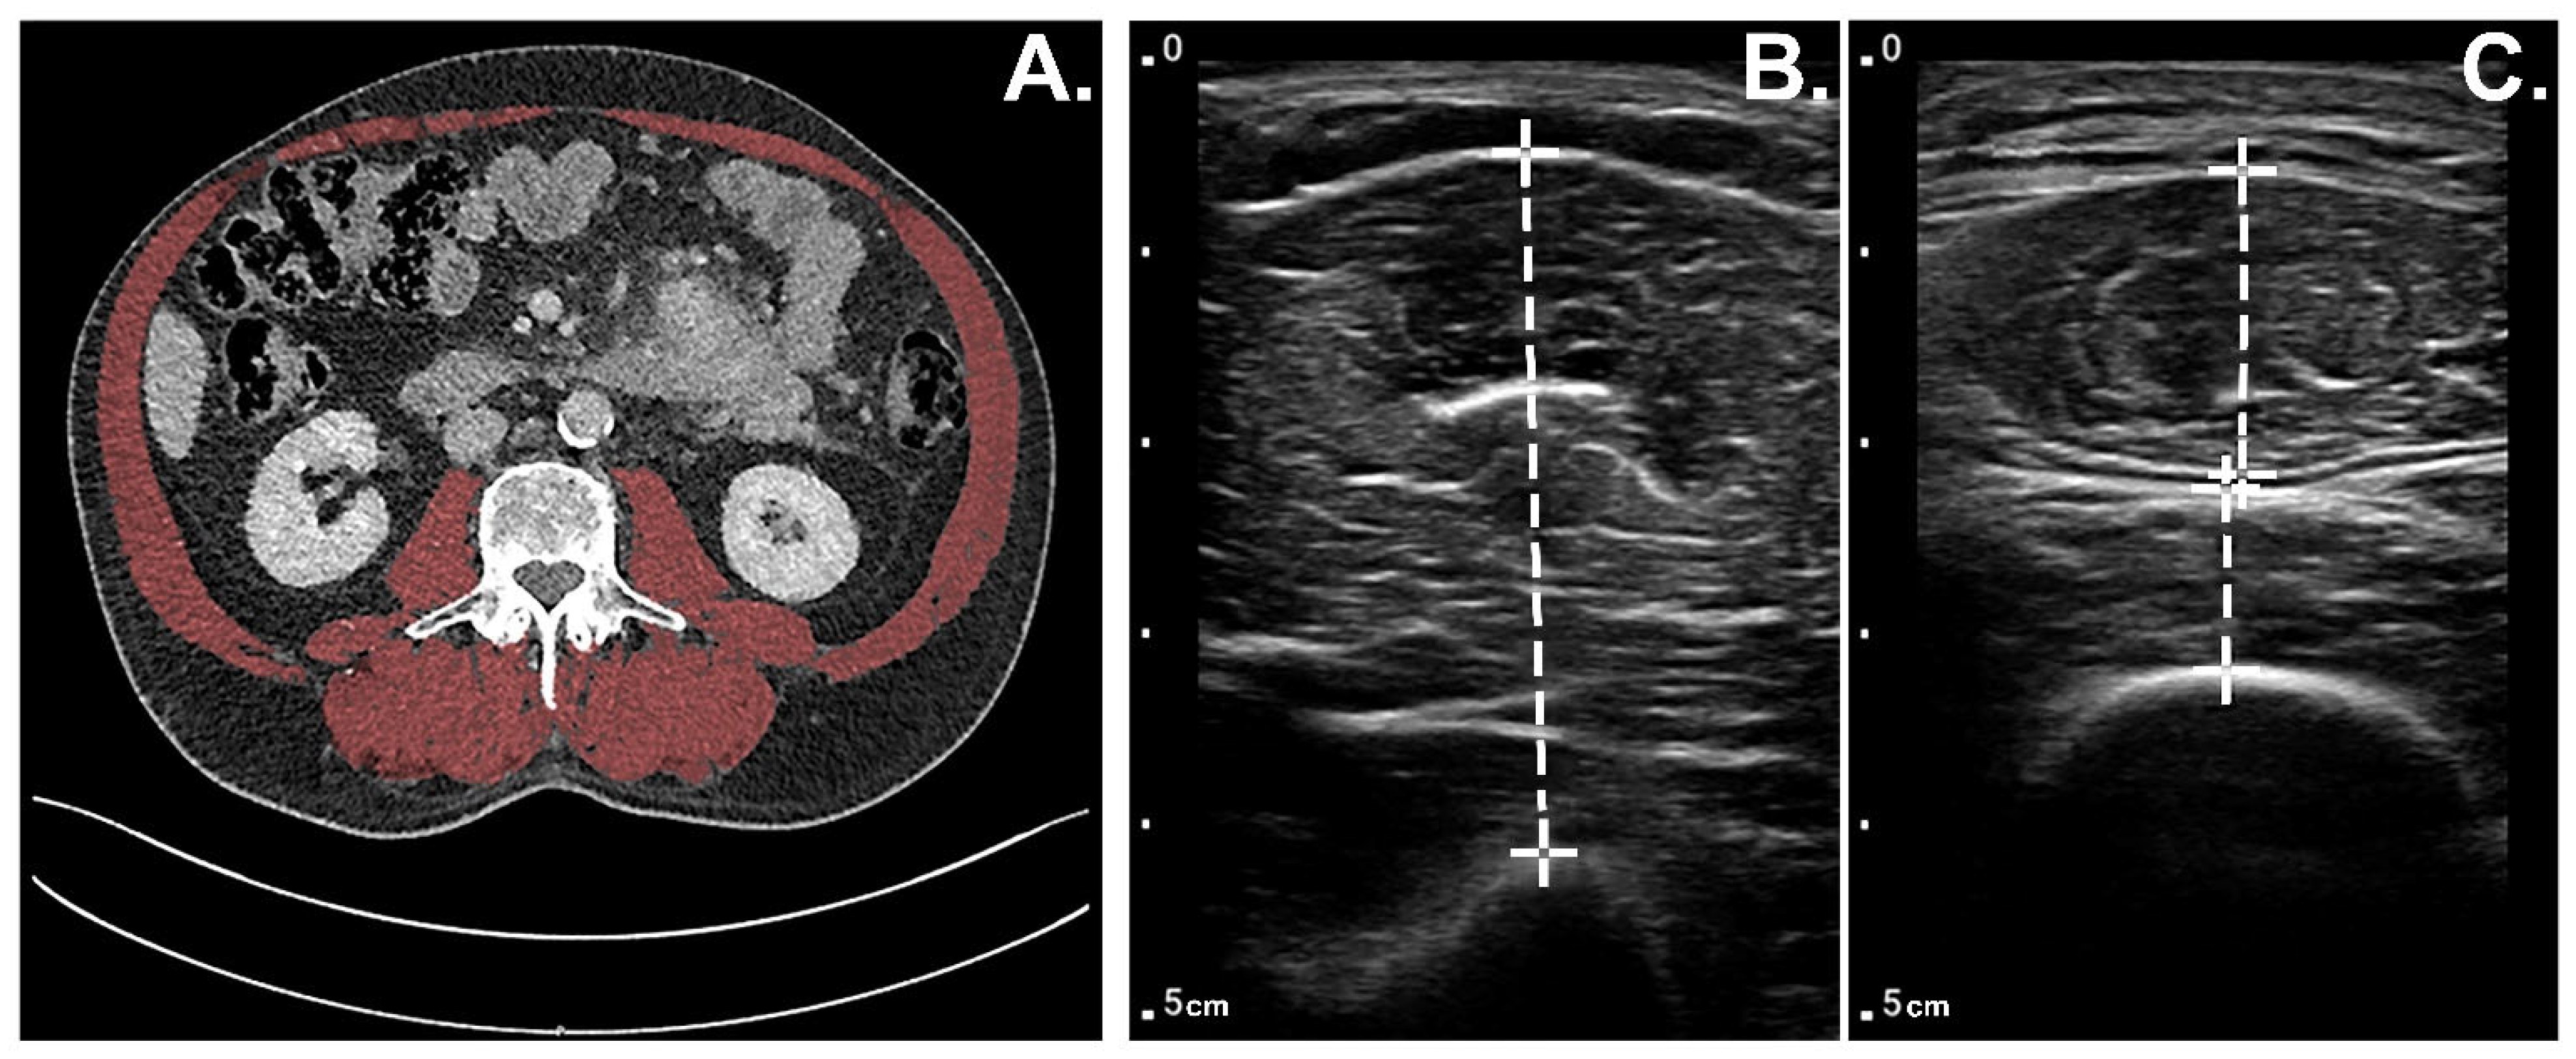

2.1. Muscle Thickness Measurements Using POCUS

2.2. Muscle Mass Measurements CT